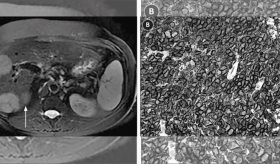

La paciente entró a evaluación de rutina con síntomas asintomáticos, tras dos años de su tratamiento con agentes antivirales de acción directa contra la hepatitis C.